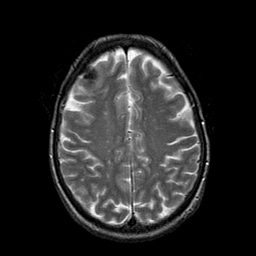

Metastatic Adenocarcinoma of the Colon: T2-weighted MR -- Slice #17

[Home][Help][Clinical] Slice 17